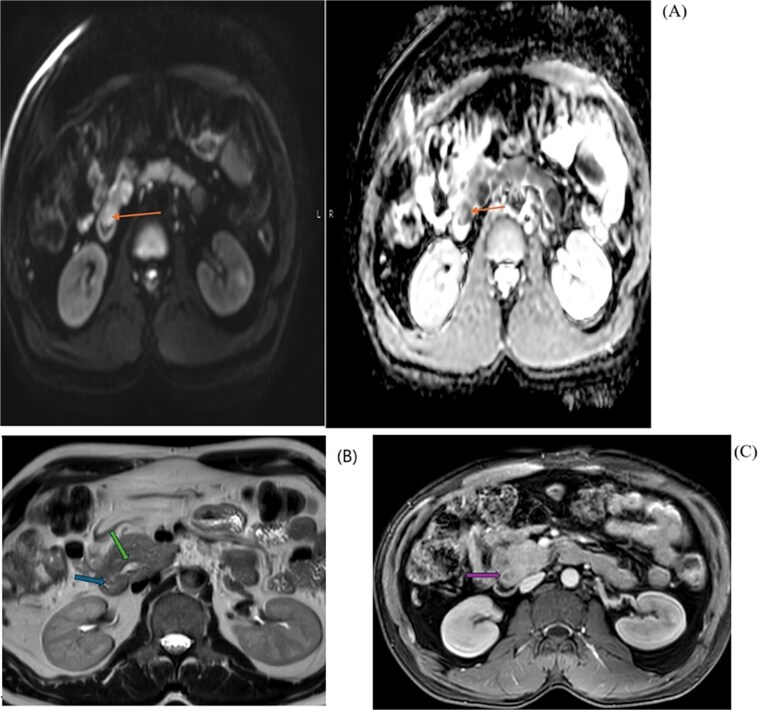

Based on the above investigation, a MRCP was planned. An axial view (Fig. 2) showed a hypo-enhancing periampullary mass lesion, which was seen showing restricted diffusion (orange arrow) measuring approximately 15 mm in size causing abrupt cut-off of the distal CBD with post IV contrast injection shows hypo enhancement of the periampullary mass (purple arrow). MRI Axial T2 Haste image at the level periampullary region shows a rounded isointense lesion in the periampullary region bulging into the lumen of the 2nd part of the duodenum (blue arrow), with dilated pancreatic duct (green arrow).